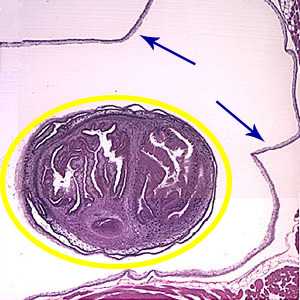

A 49-year-old male immigrant from Mexico was seen at a local medical facility specializing in neural disorders for frequent headaches and occasional seizures. Figures A and B show what was observed on a hematoxylin and eosin (H & E) stained section of lesions detected in the right frontal lobe of his brain. Figure A was taken at 40× magnification and Figure B was taken at 100× magnification. What is your diagnosis? Based on what criteria?

Figure B

This was a case of cysticercosis caused by the larval stage of Taenia solium. Diagnostic features were:

- a single protoscolex (yellow circle, Figure A) visible within the bladder wall (blue arrows, Figure A). Racemose cysticerci are characterized by proliferating, lobulated cysts without a scolex which are usually found in the ventricular system and subarachnoid space, and, rarely, in the cerebral parenchyma.